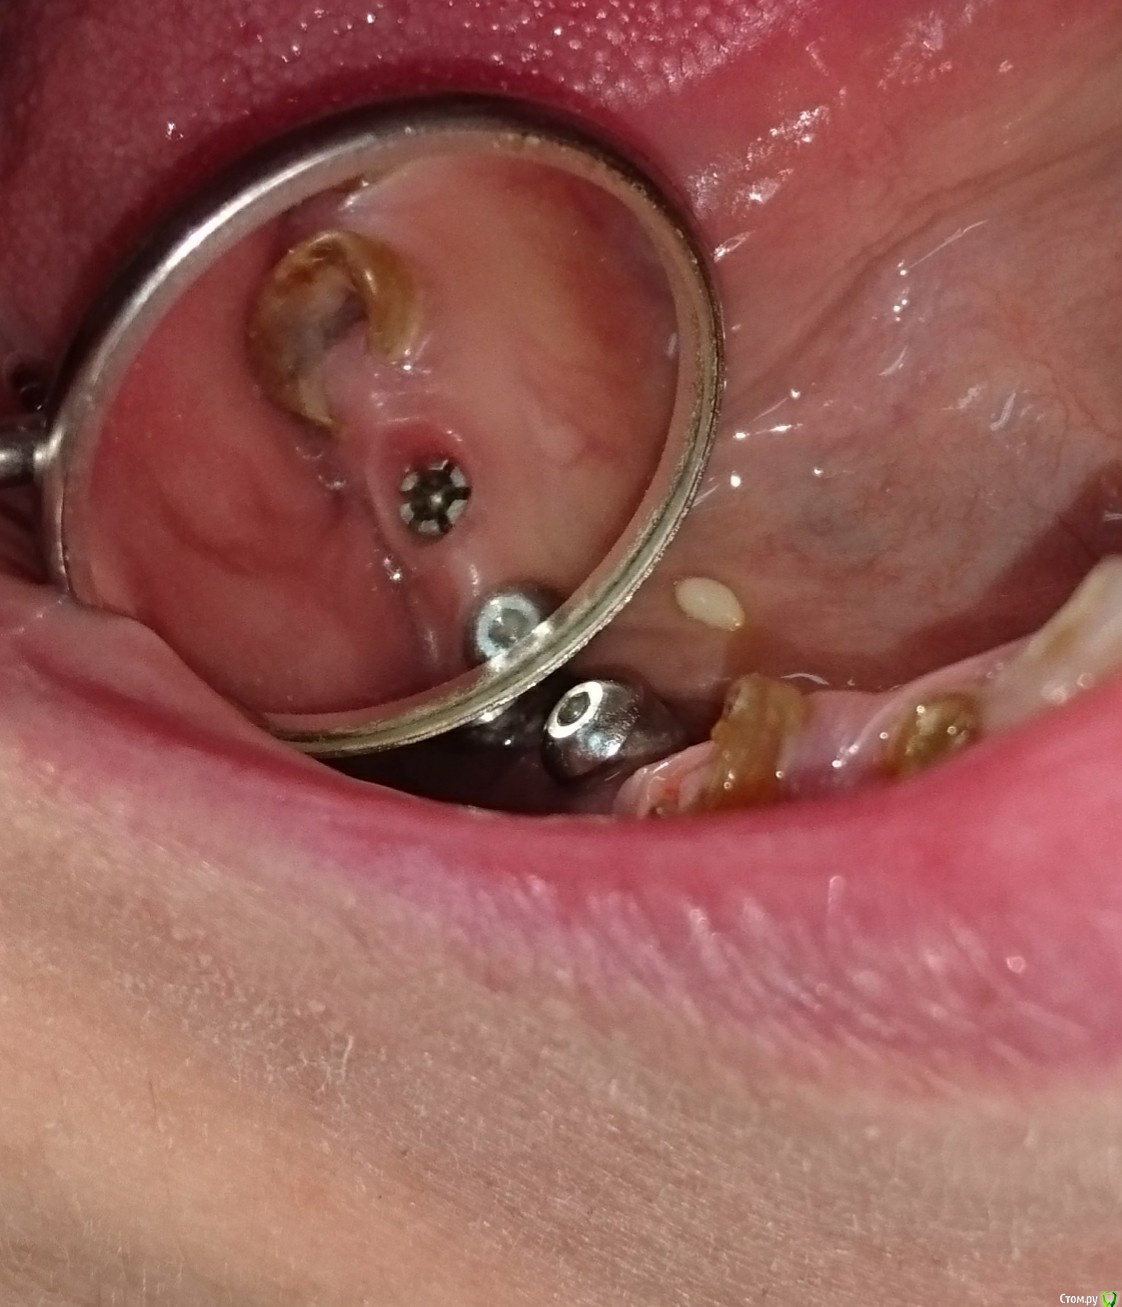

Добрый день. Пришел пациент с установленными  имплантами, какими не знает.  Путем поисков и консультаций пришли к выводу что это zimmer calcitec. У оф дилера новые модели  с внутренним 6-ом, похожее (как на картинке) было найдено только на зарубежных сайтах. Собственно вопрос, действительно ли это зиммер..и если да, есть ли возможность (желательно в Москве) найти трансферы, аналоги, абатменты?

post-30299-0-25322500-1528462287_thumb.jpg

post-30299-0-29021000-1528462298_thumb.jpg